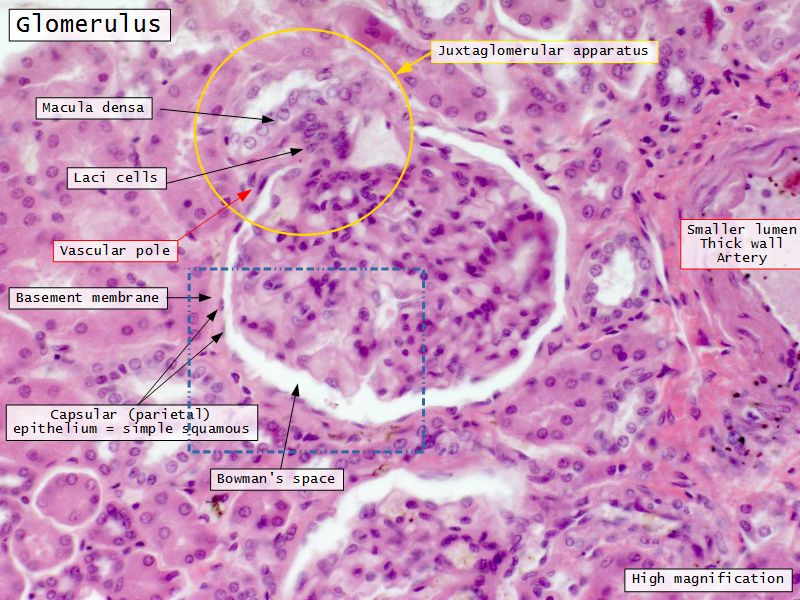

Renal corpuscle

- Tuft of capillaries

- grow into

- Blind end of nephron

- Several layers of epithelium

- Two sides

- Vascular pole

- Tubular pole

Blood flow

- Efferent arteriole

- Smooth muscle in media

- Capillaries

- Fenestrated

- Afferent arteriole

- Smooth muscle in media

Epithelium layers

- Capillary endothelium

- Visceral layer of epithelium

- Podocytes

- Resting on glomerular basement membrane

- Capsular space

- Parietal layer of epithelium

- Simple squamous epithelium

Juxtaglomerular complex

Area where distal convoluted tubule return to glomerulus and pass through the notch between the afferent and efferent arterioles. Modification of the wall of the tubule and afferent arteriole and presence of specialised cells in the connective tissue.Modifications

- Distal convoluted tubule

- Macula densa

- Narrow epithelial cells

- Nuclei densely packed

- CT cells

- Laci cells

- Similar to mesangial cells

- Afferent arteriole

- Modified smooth muscle cells

- Juxtaglomerular cells

- Secretory function